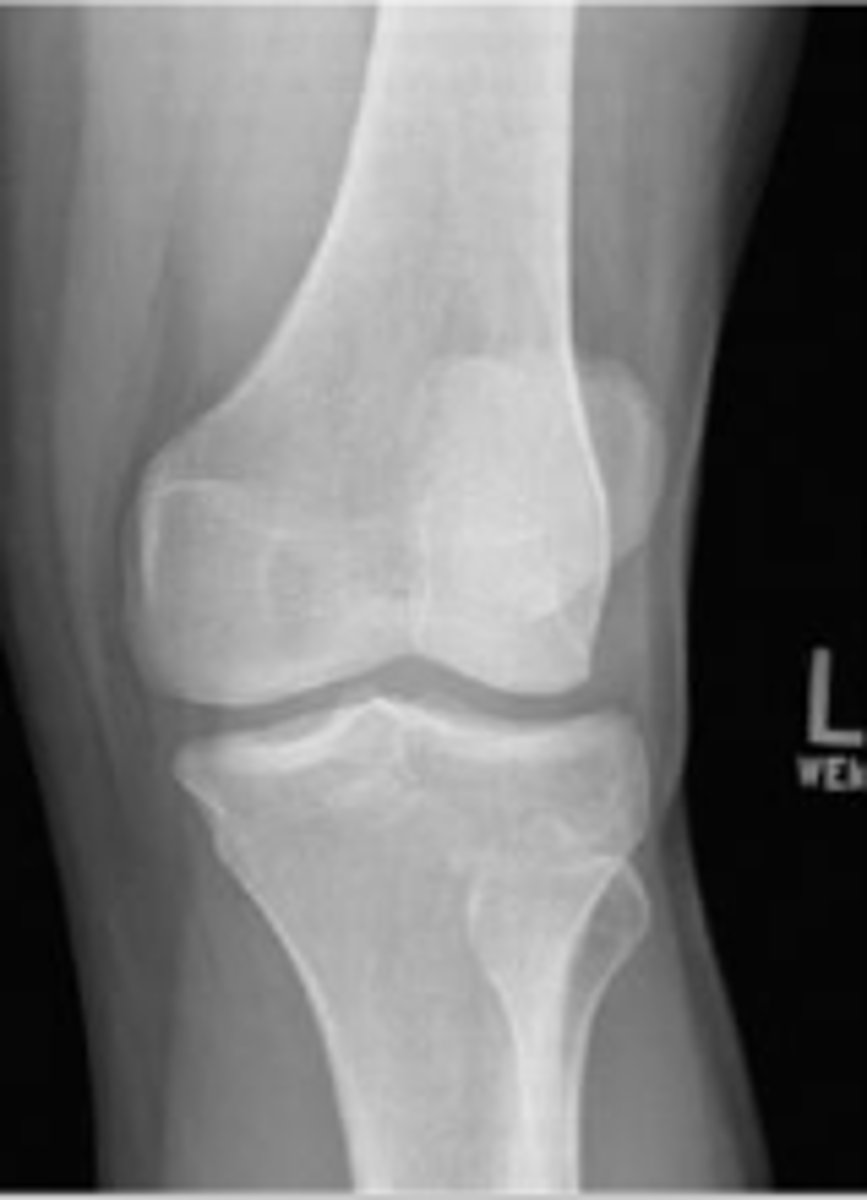

Patellofemoral joint space of the left knee

What joint space is the arrow pointing to?